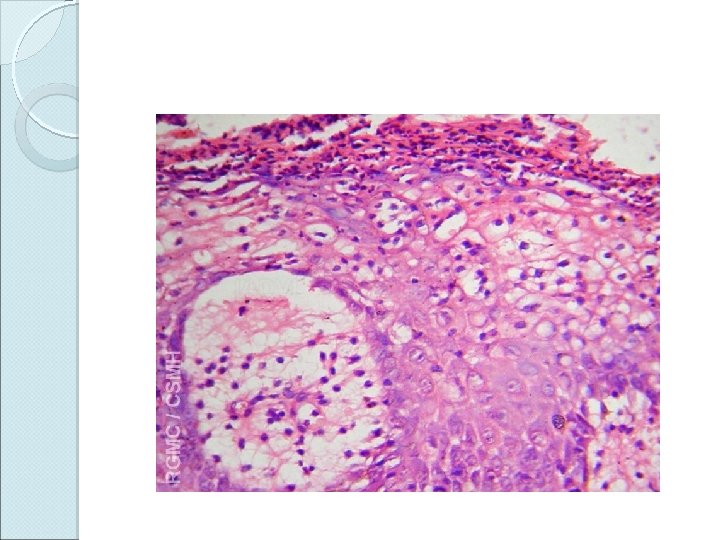

Histopathology Skin biopsy findings: Parakeratosis Microabscesses of Munro in the horny layer Absence of granular layer Regular elongation of rete ridges (camel-foot shaped) Suprapapillary thinning of st. malpighii Spongiform pustules of Kogoj Dilated and tortuous capillaries in dermal papillae Superficial perivascular inflammatory infiltrate